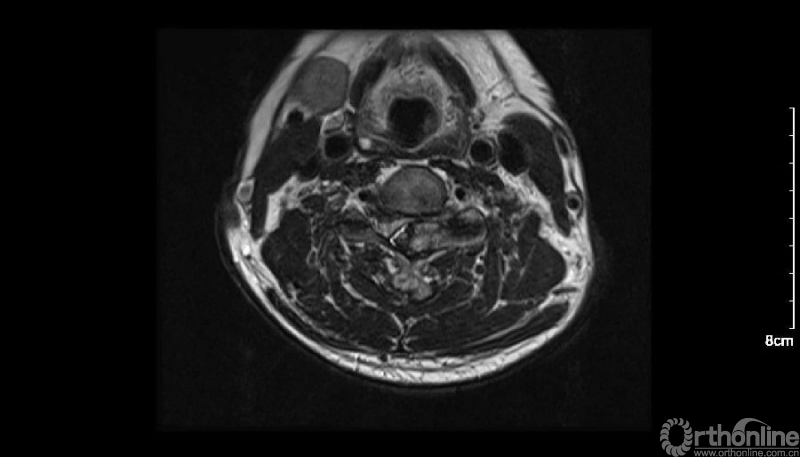

入院查体患者四肢肌张力高,双侧hoffman阳性。CT及MRI检查提示C4/5左侧关节突内缘有一巨大骨块(15mm*16mm),相应节段椎管严重狭窄。椎管内骨块的前端还有一游离骨块。

影像学资料